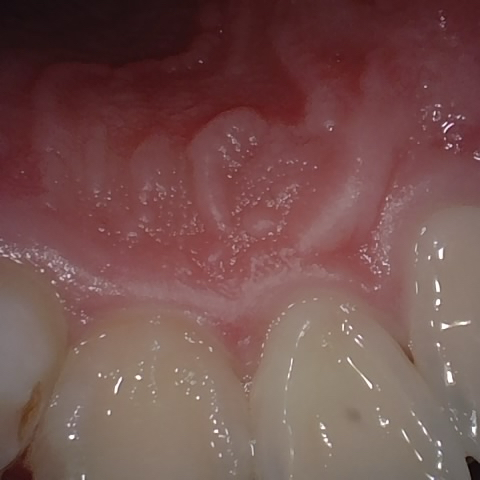

Annotated as "Good"